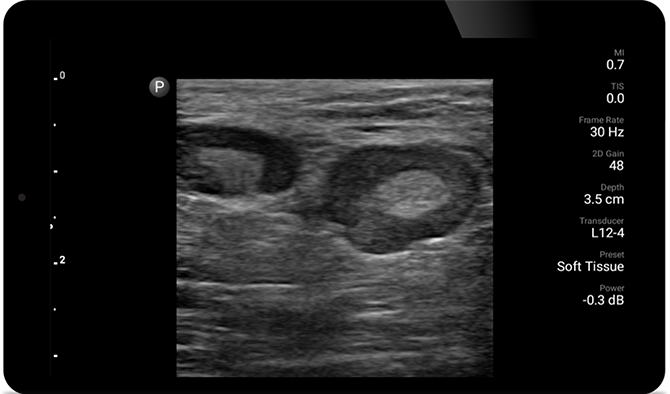

Echografieonderzoeken kunnen helpen om huidabcessen te identificeren en succesvol te behandelen.

Lumify kan helpen de subtiele details van een beeld zichtbaar te maken en afwijkende weefselstructuren bloot te leggen vanuit verschillende hoeken. Hierdoor kunt u met vertrouwen realtime beslissingen nemen, van diagnose tot herstel.

POC-echografie voor zacht weefsel